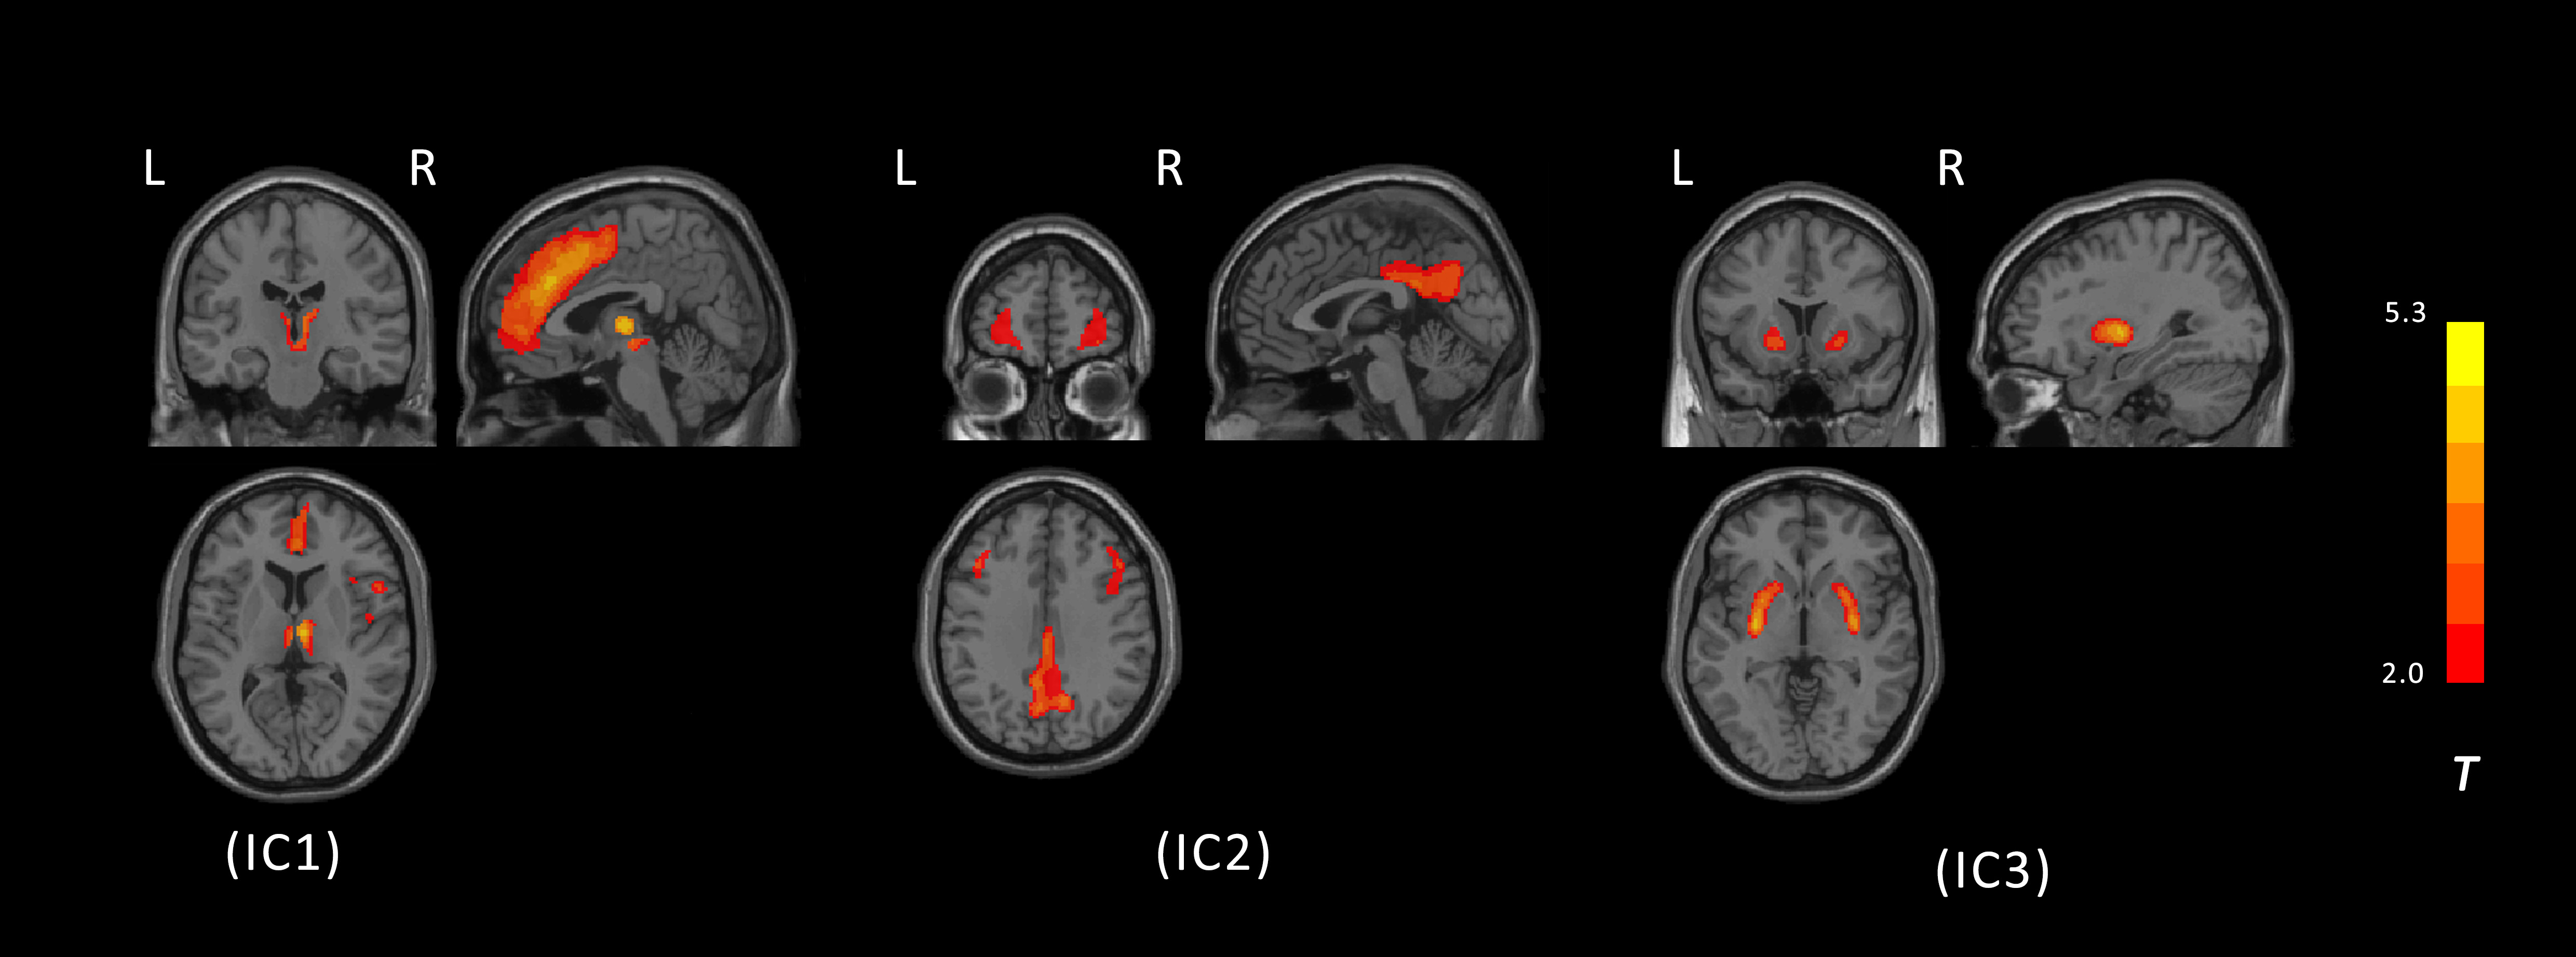

Results: Three PSP-related metabolic networks were identified: the dorsomedial thalamus-medial prefrontal cortex (dmT-mPFC) network, the posterior cingulate cortex-lateral prefrontal cortex (PCC-LPFC) network, and the putaminal network. Both the dmT-mPFC and PCC-LPFC networks showed negative correlations with overall disease severity, while the dmT-mPFC and putaminal networks were inversely associated with disease duration. The PCC-LPFC network primarily reflected cognitive impairment and parkinsonism, whereas the dmT-mPFC network was linked to gait and midline disturbances, as well as ocular motor dysfunction. Both networks demonstrated a strong association with striatal DAT binding.

PSP-related networks